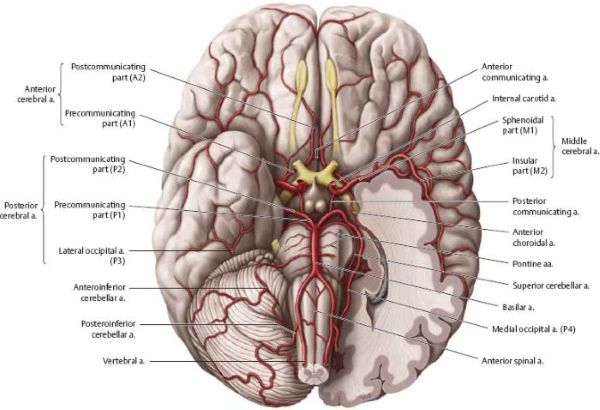

ხერხემლის არტერია (VA), რომელიც ჩვეულებრივ იწყება ლავიწქვეშა არტერიიდან (მარჯვენა - მხარ-თავის ღეროდან, მარცხენა - პირდაპირ ლავიწქვეშა არტერიიდან), იყოფა ოთხ ანატომიურ სეგმენტად[1, 2]:

- V1 (ხვრელამდელი სეგმენტი): საწყისიდან განივ ხვრელში შესვლამდე, ჩვეულებრივ კისრის C6 მალის დონეზე (ზოგჯერ C5 ან C7).

- V2 (ხვრელოვანი სეგმენტი): ადის ვერტიკალურად C6-დან C2 მალების განივი ხვრელების გავლით.

- V3 (ატლანტის ან ექსტრადურალური სეგმენტი): გამოდის C2-ის განივი ხვრელიდან, მიემართება უკან და მედიალურად C1 (ატლანტის) ლატერალური მასის გარშემო, გადის C1-ის განივ ხვრელში და ჰორიზონტალურად მიემართება C1-ის უკანა რკალის ღარში, სანამ გაივლის უკანა ატლანტო-ოკციპიტალურ მემბრანას და მაგარ გარსს კეფის დიდი ხვრელის მახლობლად.

- V4 (ინტრადურალური სეგმენტი): იწყება მაგარი გარსის გახვრეტის შემდეგ, მიემართება ზევით მოგრძო ტვინის წინ და უერთდება კონტრალატერალურ ხერხემლის არტერიას პონტომედულარულ (ხიდ-მოგრძო ტვინის) საზღვარზე, რათა წარმოქმნას ძირითადი (ბაზილარული) არტერია.

V4 სეგმენტიდან გამოდის მნიშვნელოვანი ტოტები, მათ შორის მცირე შეღწევადი არტერიები, რომლებიც კვებავენ მოგრძო ტვინს და, რაც მთავარია, ნათხემის ქვედა უკანა არტერია (PICA) [1, 2]. PICA ჩვეულებრივ იწყება დისტალური V4 სეგმენტიდან, მარყუჟს აკეთებს მოგრძო ტვინის გარშემო (კვებავს მის ლატერალურ ზედაპირს) და შემდეგ სისხლით ამარაგებს ნათხემის ქვედა ზედაპირს და მეოთხე პარკუჭის ქოროიდულ წნულს [1, 2]. PICA-ს საწყისსა და მომარაგების არეალში არსებობს მნიშვნელოვანი ანატომიური ვარიაციები [1, 2].

კოლატერალური სისხლმომარაგება შეიძლება განხორციელდეს V2 სეგმენტის კუნთოვან ტოტებსა და გარეთა საძილე არტერიის (მაგ., კეფის არტერია) ან ფარისებრ-კისრის ღეროს (მაგ., კისრის ასწვრივი არტერია) ტოტებს შორის არსებული ანასტომოზების მეშვეობით [1]. ხერხემლის არტერიის ჰიპოპლაზია (განუვითარებლობა) ხშირია (დაახლოებით 10%), რაც კონტრალატერალურ ხერხემლის არტერიას და კოლატერალურ გზებს კრიტიკულად მნიშვნელოვანს ხდის დომინანტური ხერხემლის არტერიის ოკლუზიის შემთხვევაში [1].